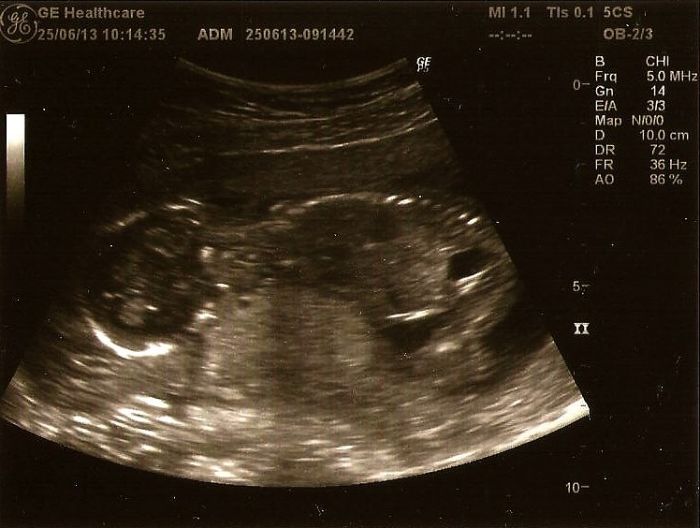

Rosteme teda šíleně,bříško už neschovám a mám navrch 2kg..Začali jsme dneska 18tt a ráno jsme měli konttolu..Vše je v pořádku,riziko downu 1:50 000,scr.negativní a máme něco mezi 14-15cm takže krásně rosteme,ale mrňouse zatim necitim..Zatim to vypadá na chlapečka,ale prý to ještě není jednoznačné,tak se nemáme lekat kdyby nám za měsíc řekli holčičku na screeningu..

Průtoky jsou taky v pořádku a mrňous celou kontrolu prospal a nenechal se vyvést z míry..

Barco040 máš krásné bříško. Já tím že mám docela velkou nadváhu tak mám bříško kulaté celé ne jen u spodu, ale nevadí mi to zase tak moc.